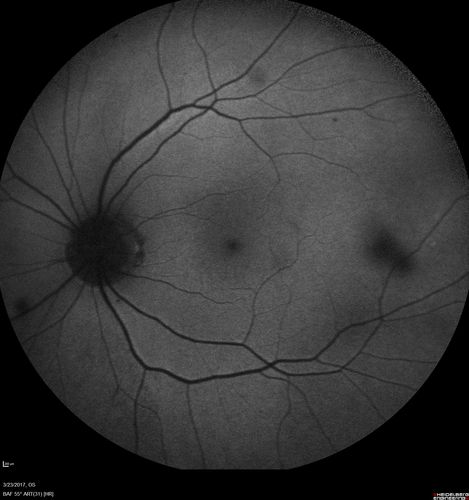

CRVO with Paracentral Acute Middle Maculopath - PAMM

56 year old woman with sudden vision loss, hemorrhages in all four quadrants.  FA shows good retinal circulation.  The OCT shows PAMM lesions in the affected eye.  Vision did improve on second visit from 20/160 to 20/60 in about a month